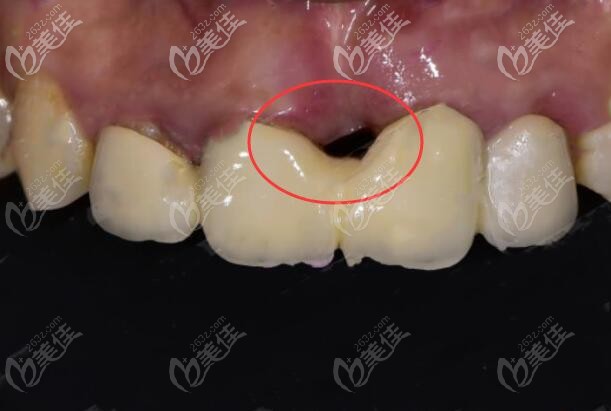

種牙后這么大的黑洞,要是我非哭死不可▼

事后我不由感嘆,做種植牙,一定要多咨詢幾家醫(yī)院,選擇一個(gè)靠譜的醫(yī)生,否則,后果不堪想象!